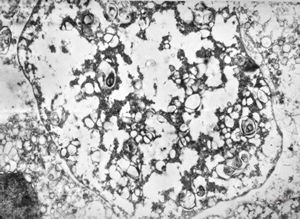

M,50y. | Pneumocystis carinii